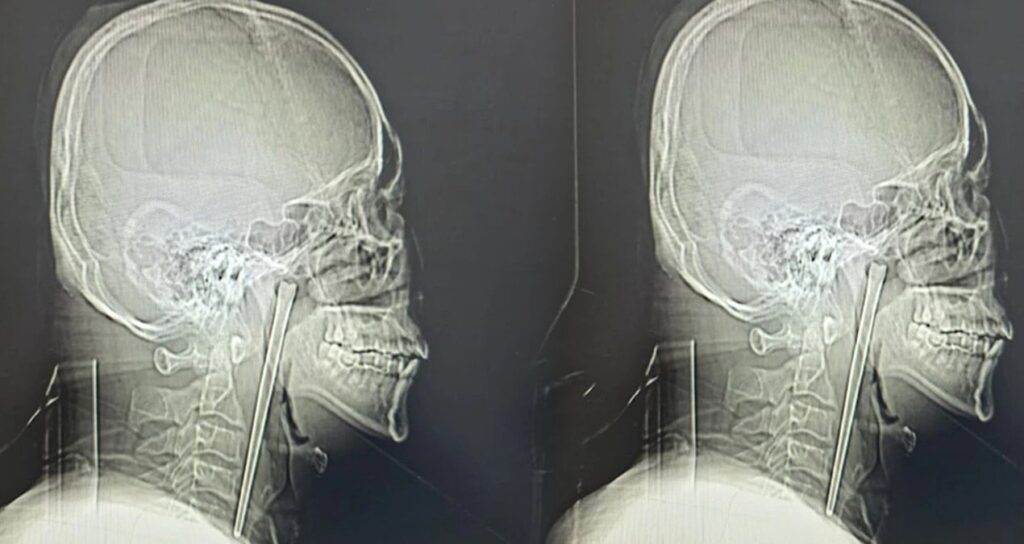

46 yaşındaki bir adam, sekiz yıl önce yuttuğu 12 santimetrelik metal yemek çubuğuyla yaşamaya devam etti. Olay, Çin’in Liaoning eyaletindeki Dalian kentinde gerçekleşti. Yıllar boyunca süren rahatsızlık ve ağrılar, hastanın sonunda hastaneye başvurmasına neden oldu.

Dalian Belediye Merkez Hastanesi’nde yapılan röntgen muayenesinde, hastanın boğazında metal bir milin bulunduğu tespit edildi. Bay Wang, doktorların soruları üzerine, yemek yerken yanlışlıkla yuttuğu metal çubuğu sekiz yıl boyunca taşıdığını doğruladı.

Dalian Teknoloji Üniversitesi Bağlı Merkez Hastanesi Kulak Burun Boğaz Bölümü uzmanları, hayati damarlara ve mukoza dokusuna zarar verme riski bulunan bu cismi çıkarmak için minimal invaziv (kapalı cerrahi) yöntemi tercih etti. Dr. Huang Weipeng ve ekibi tarafından gerçekleştirilen operasyonla, 12 santimetre uzunluğundaki paslanmaz çelik yemek çubuğu dokulardan ayrılarak tek parça halinde çıkarıldı. Bu ilginç vaka, uzun süreli sağlık sorunlarının ihmal edilmemesi gerektiğini bir kez daha gözler önüne serdi.